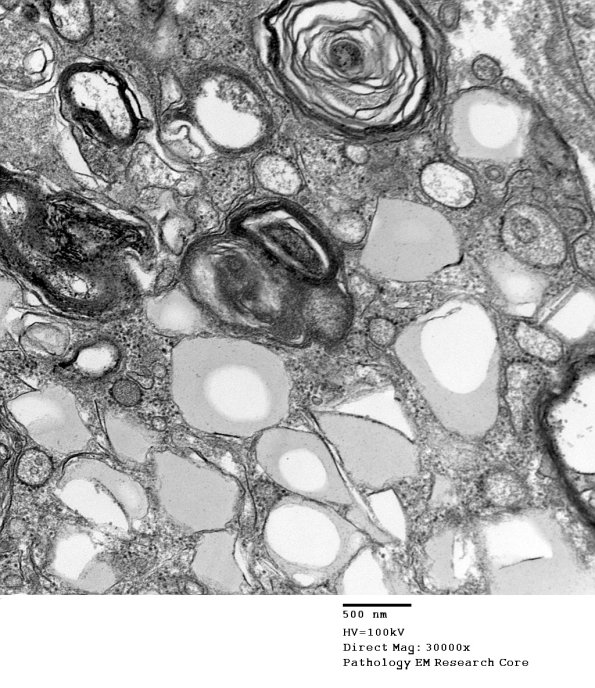

Higher magnification image of the macrophage cytoplasm showing myelin debris and fat droplets without a basement membrane.